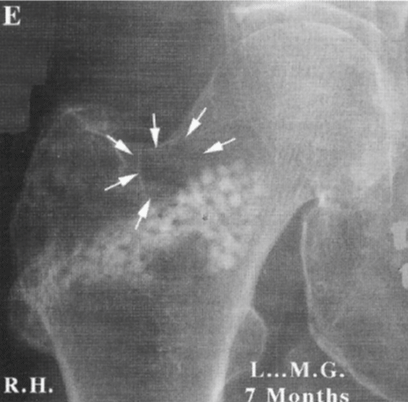

The osseous demineralisation is confirmed by the osteodensitometry. Note the very poor quantity of cancellous bone left in the Ward’s triangle: 0,035 g/cm2 (Figure 2B).

Post-operative densitometry (10) (Figure 3)

The post-operative osteodensitometry shows major reconstruction of the bone structure with a 20% increase in the high-risk zone (Ward’s triangle) 7 months after surgery, and 18 months after surgery the mineralization is almost 80%. A question remains: why 7 months after graft the intertrochanteric densitometry is so high in the Ward’s Area: more than 120%? Normally, it is impossible to get more than 100 % of the normal physiological amount. The 120% is due to the sum of the calcium in the femoral neck (walls and lamellae), plus the remaining natural coral; and, at last, the new bone formed. 20 months later, as it is shown below, the decreasing percentage of new bone in all analyzed sites supports this analysis [9-12].